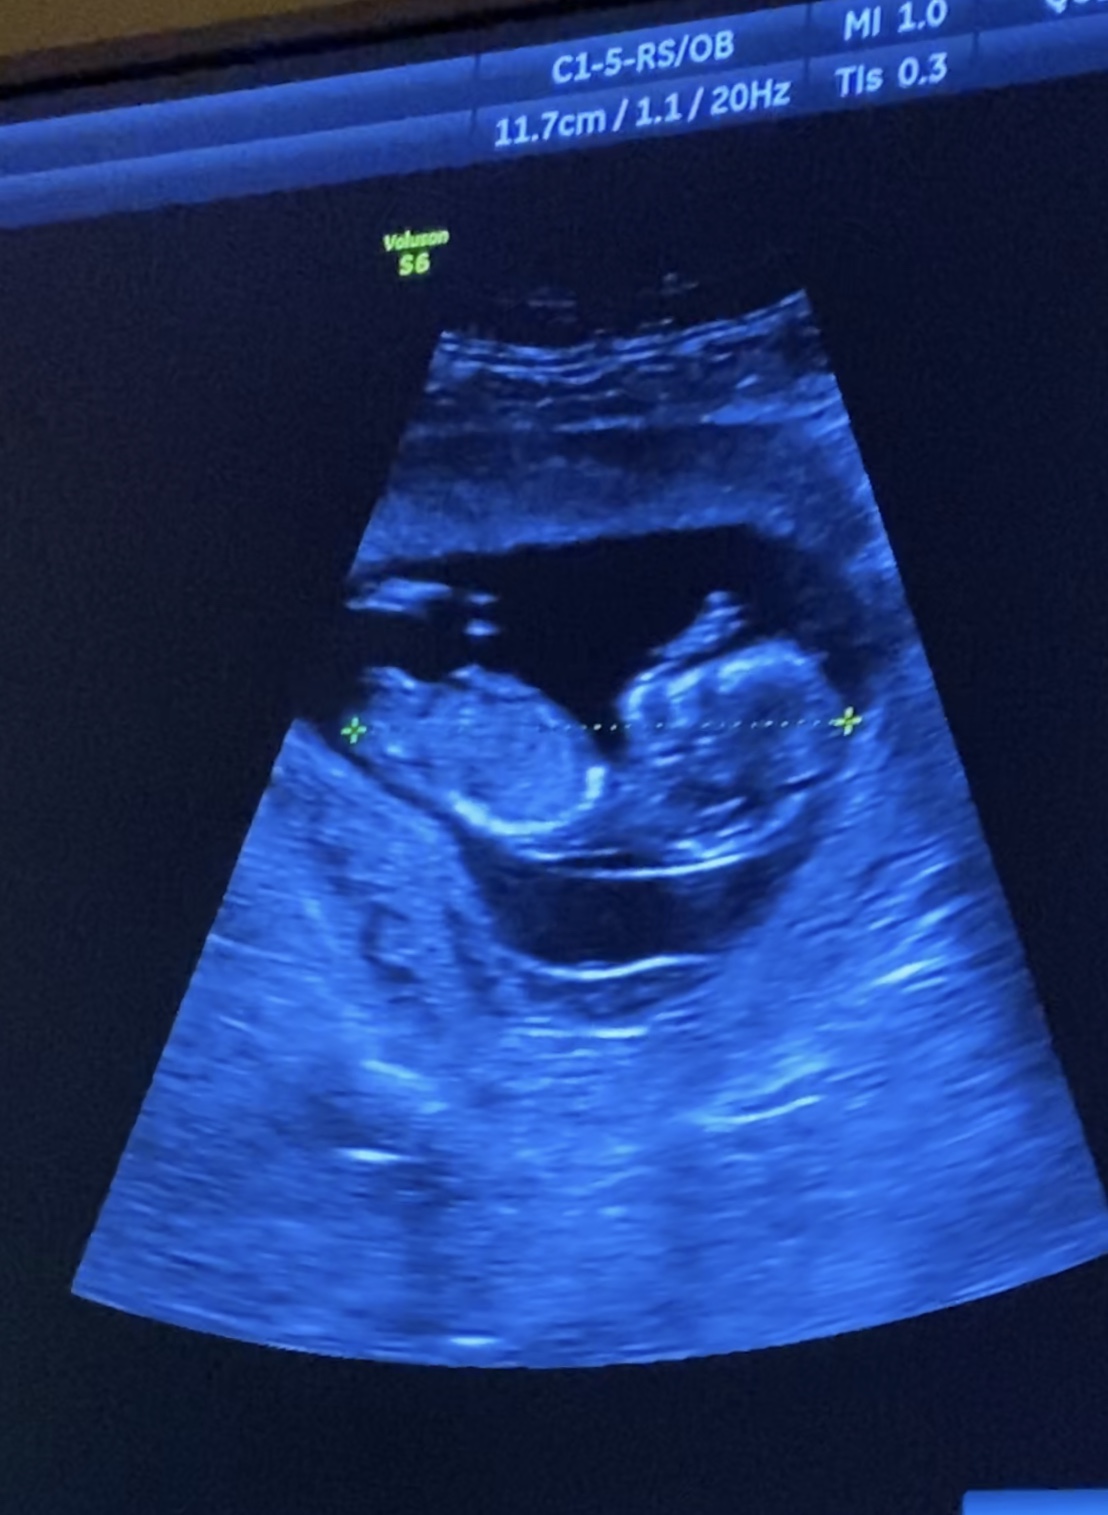

I also have this shot, but I知 not sure if that痴 a leg or a nub or what

The bottom pic is the nub but it's partly cut off. I'll give the smallest, slightest pink lean on that but it's way too early for my liking (nubs can and often do still rise after this stage) and it's also not the clearest of nubs.